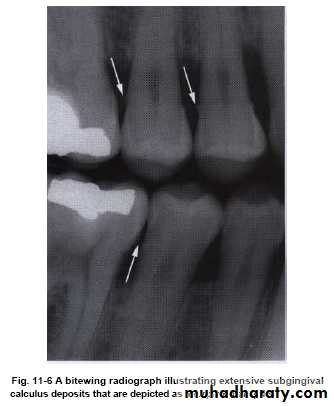

• It can be seen in radiograph (radiopaque projections that protrude into interdental space).

Diagnosis of dental calculus

• Subgingival calculus